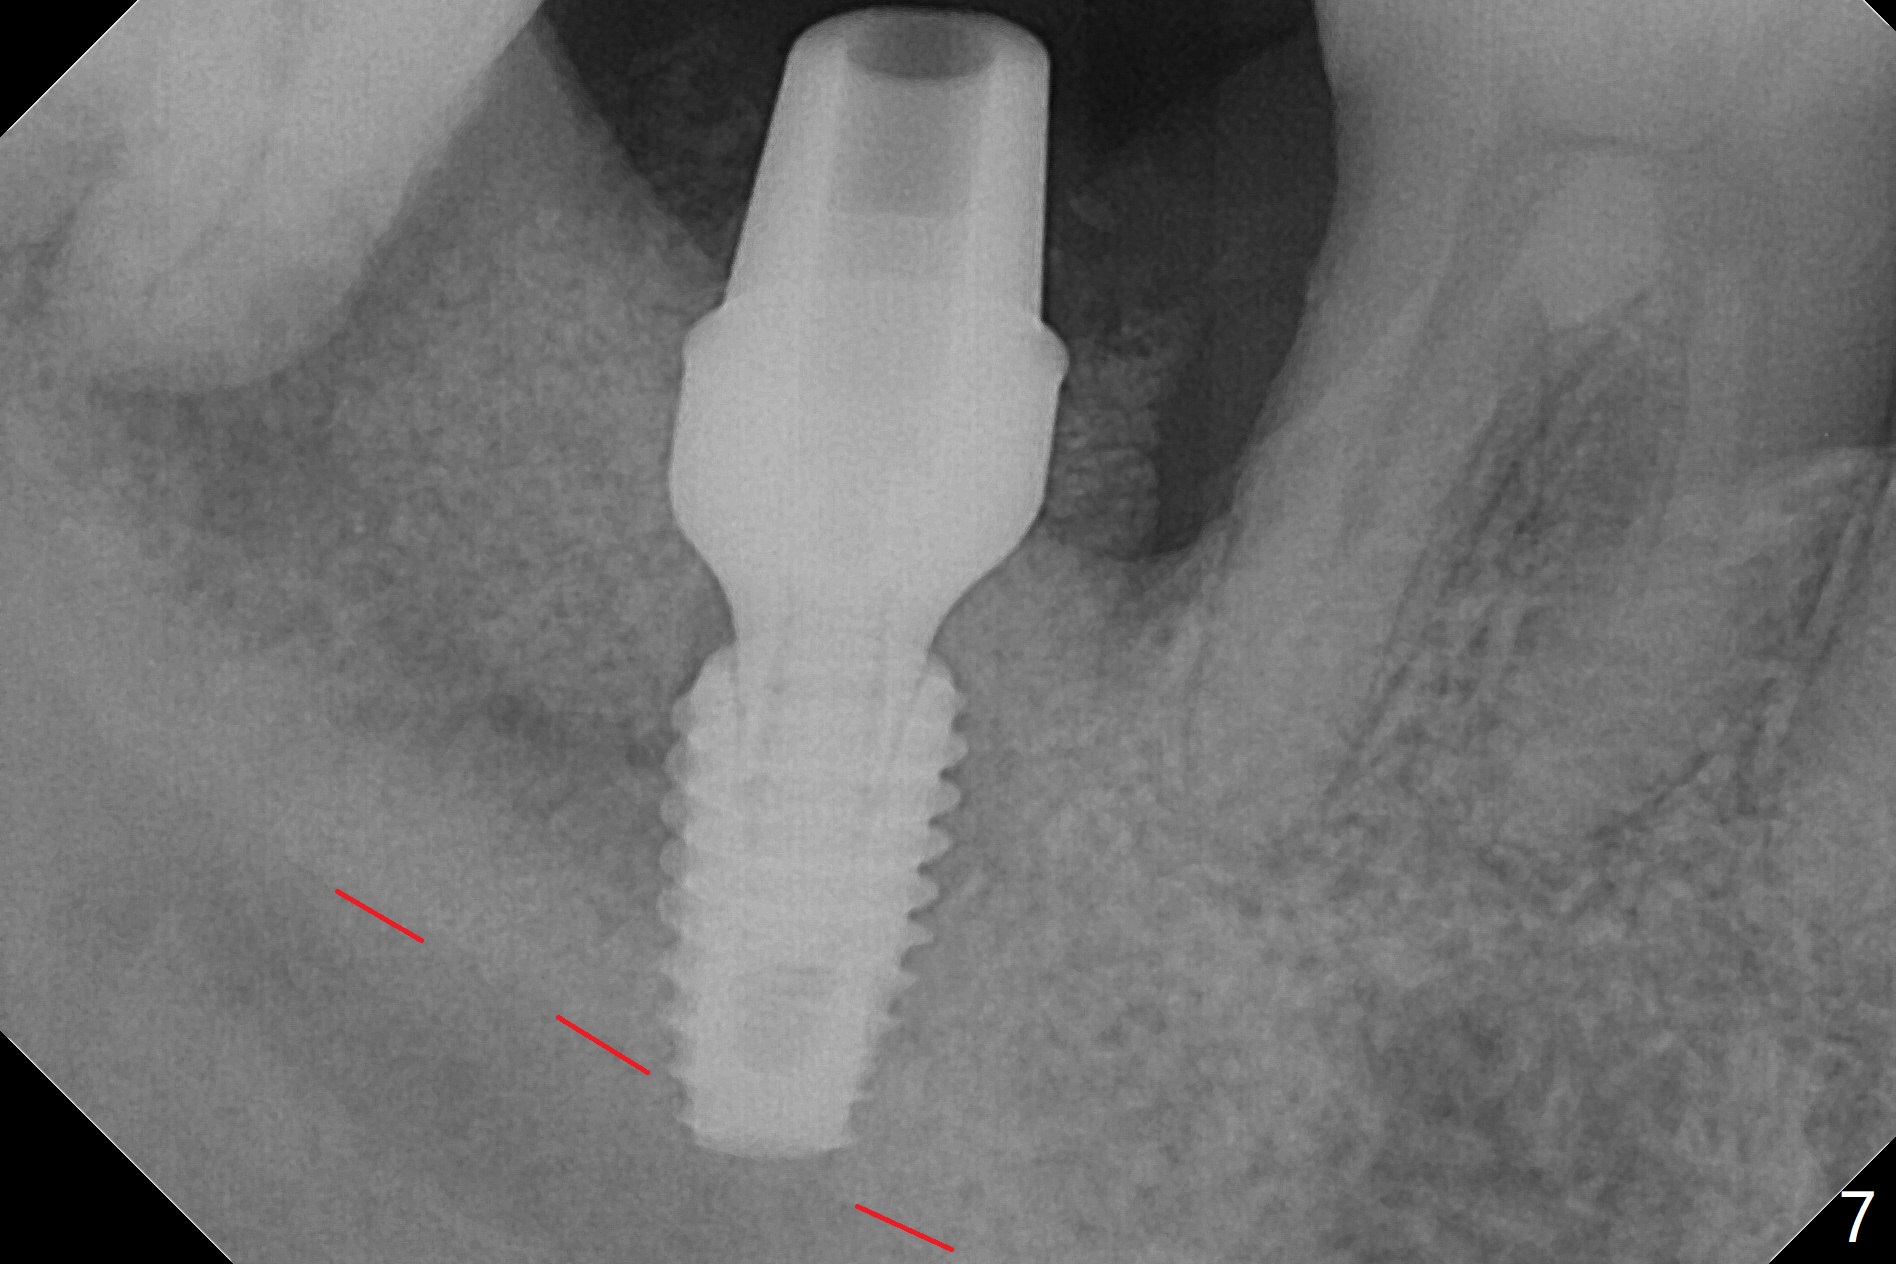

The affected tooth (#31, Fig.1) has severe buccal gingival recession with mobility III. After extraction and removal of granulation tissue, osteotomy is initiated in the middle of the fused socket using IS drills with 4 mm stopper (Fig.2,3). Following sequential osteotomy until 4 mm drill, a 4.5x10 mm IS dummy implant does not achieve primary stability, whereas 5x10 mm one does (Fig.4,5). Due to limited bone height confirmed intraoperatively, a shorter UF implant is placed with insertion torque 30 Ncm (Fig.6,7) with ~ 4.5 mm implant threads exposed coronally. After placing a 6.5x5(5) mm abutment, Vanilla Graft (*) and PRF membrane and collagen plug, an immediate provisional is fabricated to close the remaining socket. The tooth #32 is kept initially to increase the stability of the provisional and removed 8 day postop because of discomfort. A 5.5(2.5) mm mill abutment is changed to 3 months postop. The implant seems ready for impression 6 months postop (Fig.8). The bone graft remains around the apical portion of the mill abutment with apparently new bone formation around the coronal portion of the implant10 months postop (Fig.9); porcelain (*) has been added to close the mesial gingival embrasure and proximal contact gap. Due to unfavorable crown/implant ratio and poor trajectory, the crown/abutment becomes loose once post 1st cementation. Guided surgery would avoid the trajectory isssue.